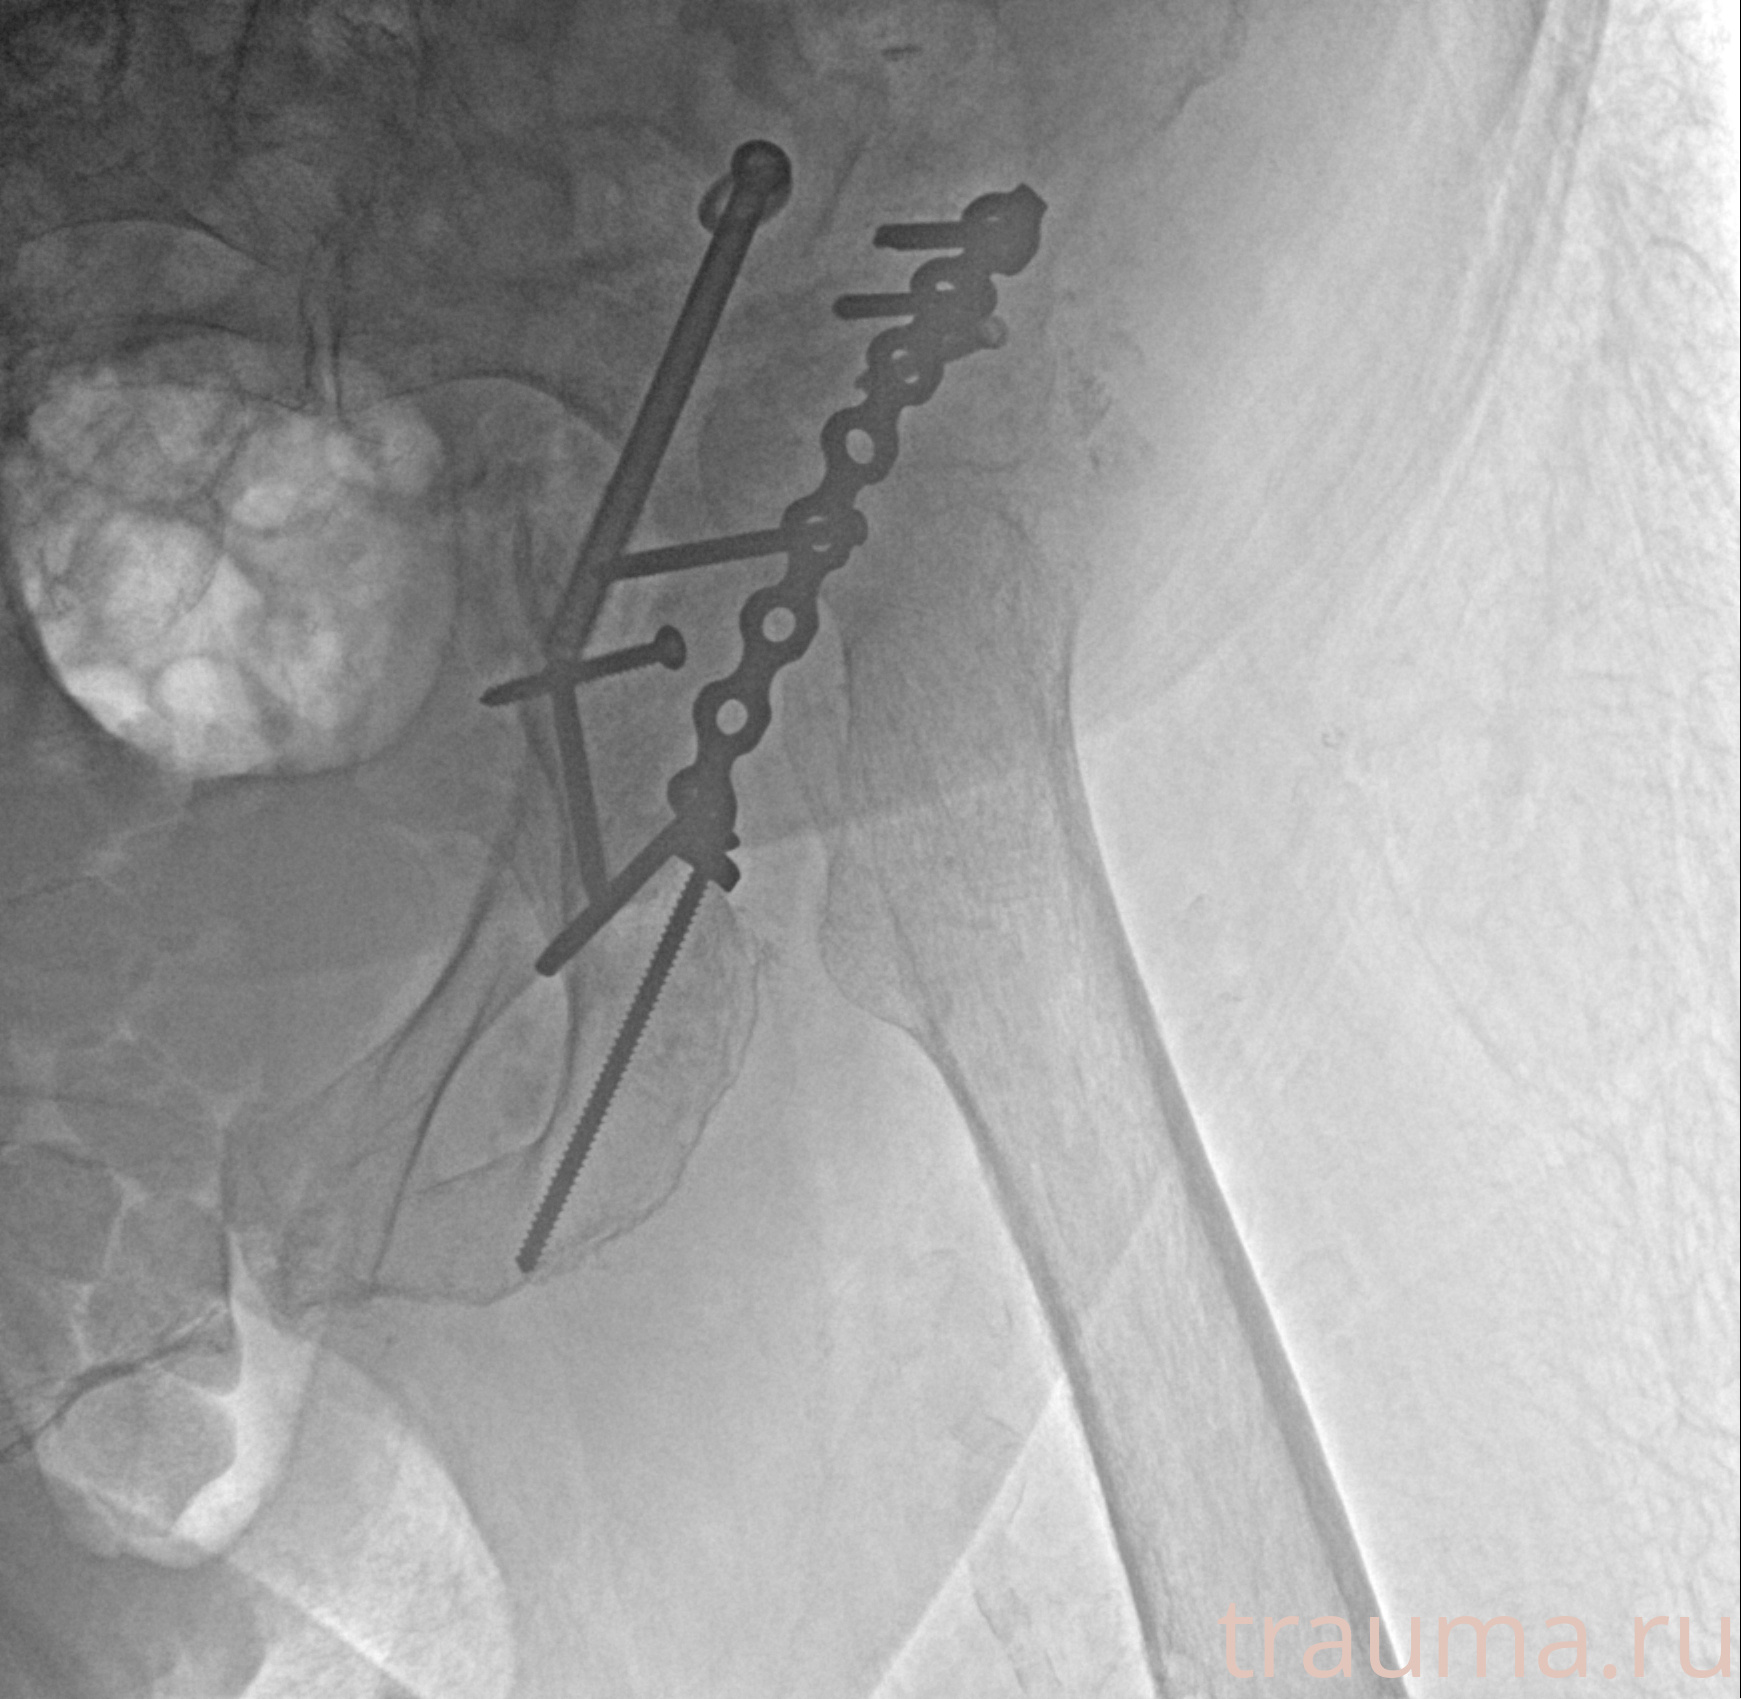

Рентгенограммы